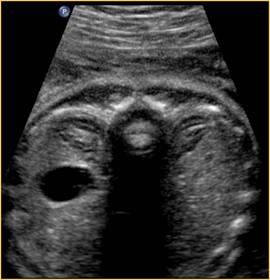

kidney / testis crisscross

What is the size of the adrenals in a fetus?

20x larger in fetus than adults

can mimic kidneys